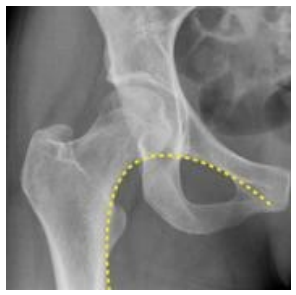

Qual o nome da linha traçada na radiografia abaixo?

enunciado 492737-1